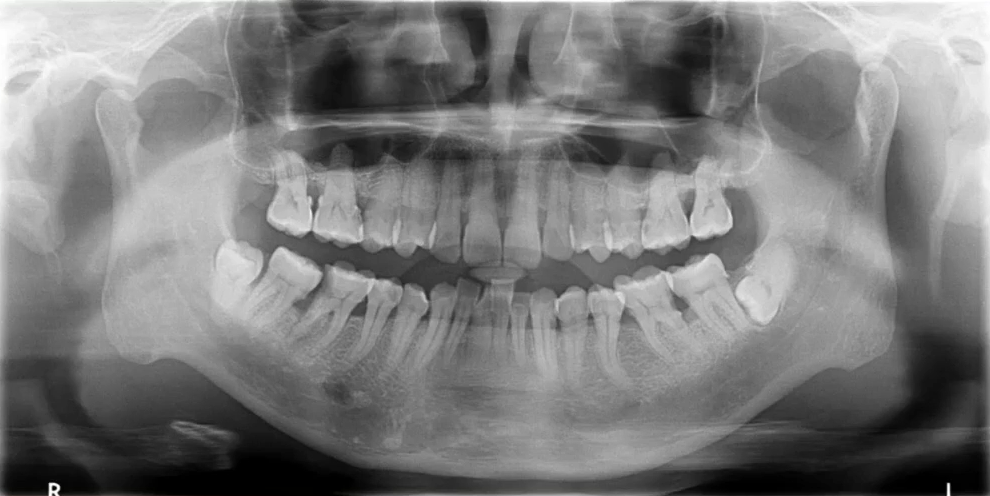

一、理想曲断影像

中线左右对称,牙齿排列呈微笑弧形,片子左右两边相对对称,能清晰显示颞下颌关节、上下牙列的牙根,图像的对比度和分辨率较好。

1. 全面显示牙列:牙体疾病初步诊断

比如下面这张片子显示出的龋坏合并根尖周炎。